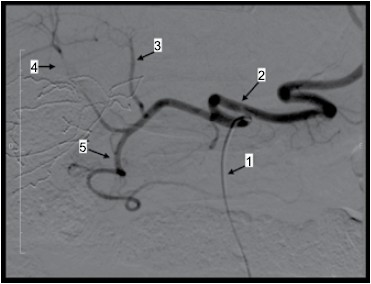

Observe a imagem.

(Arquivo pessoal: imagem usada com autorização)

Considere o exame angiográfico apresentado e assinale a alternativa correta.